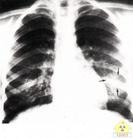

X線胸片 X線胸片和心電圖應常規檢查並在以後必要時複查

1.X線胸片無肺部併發症的低體溫嬰兒X線胸片顯示肺野清晰系肺血管收縮所致如血管紋理增粗出現斑片狀或團塊狀影應警惕肺出血的可能